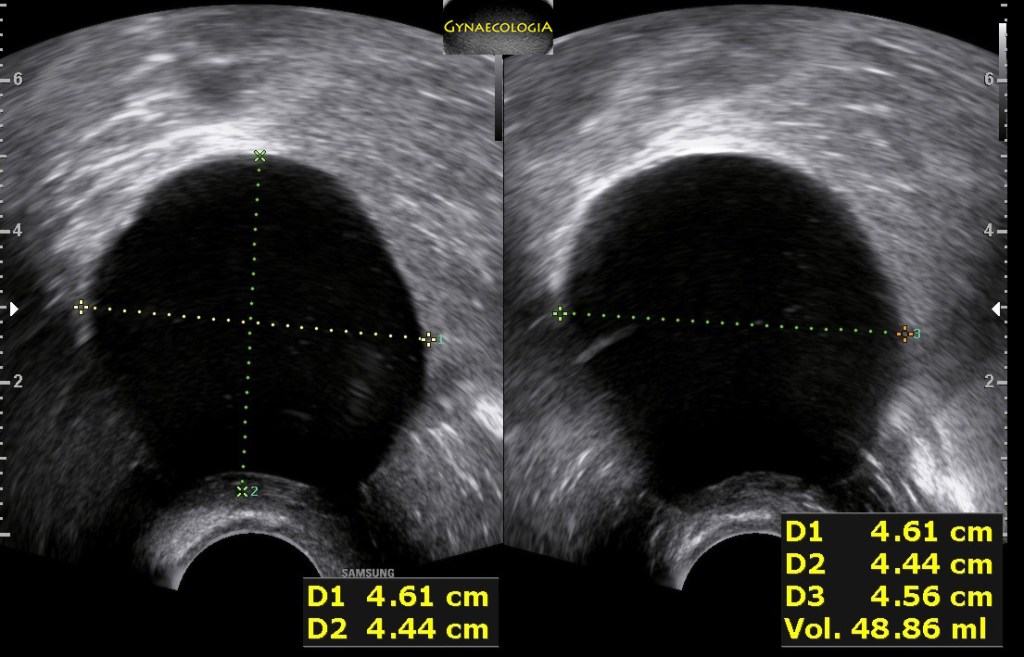

Ultrasound findings

- Frequently large, unilateral, cystic mass.

- Usually multilocular.

- Smooth walls.

- Contains small cystic components or honeycomb-like loculi.

- Intralocular fluid of varying echogenicity.